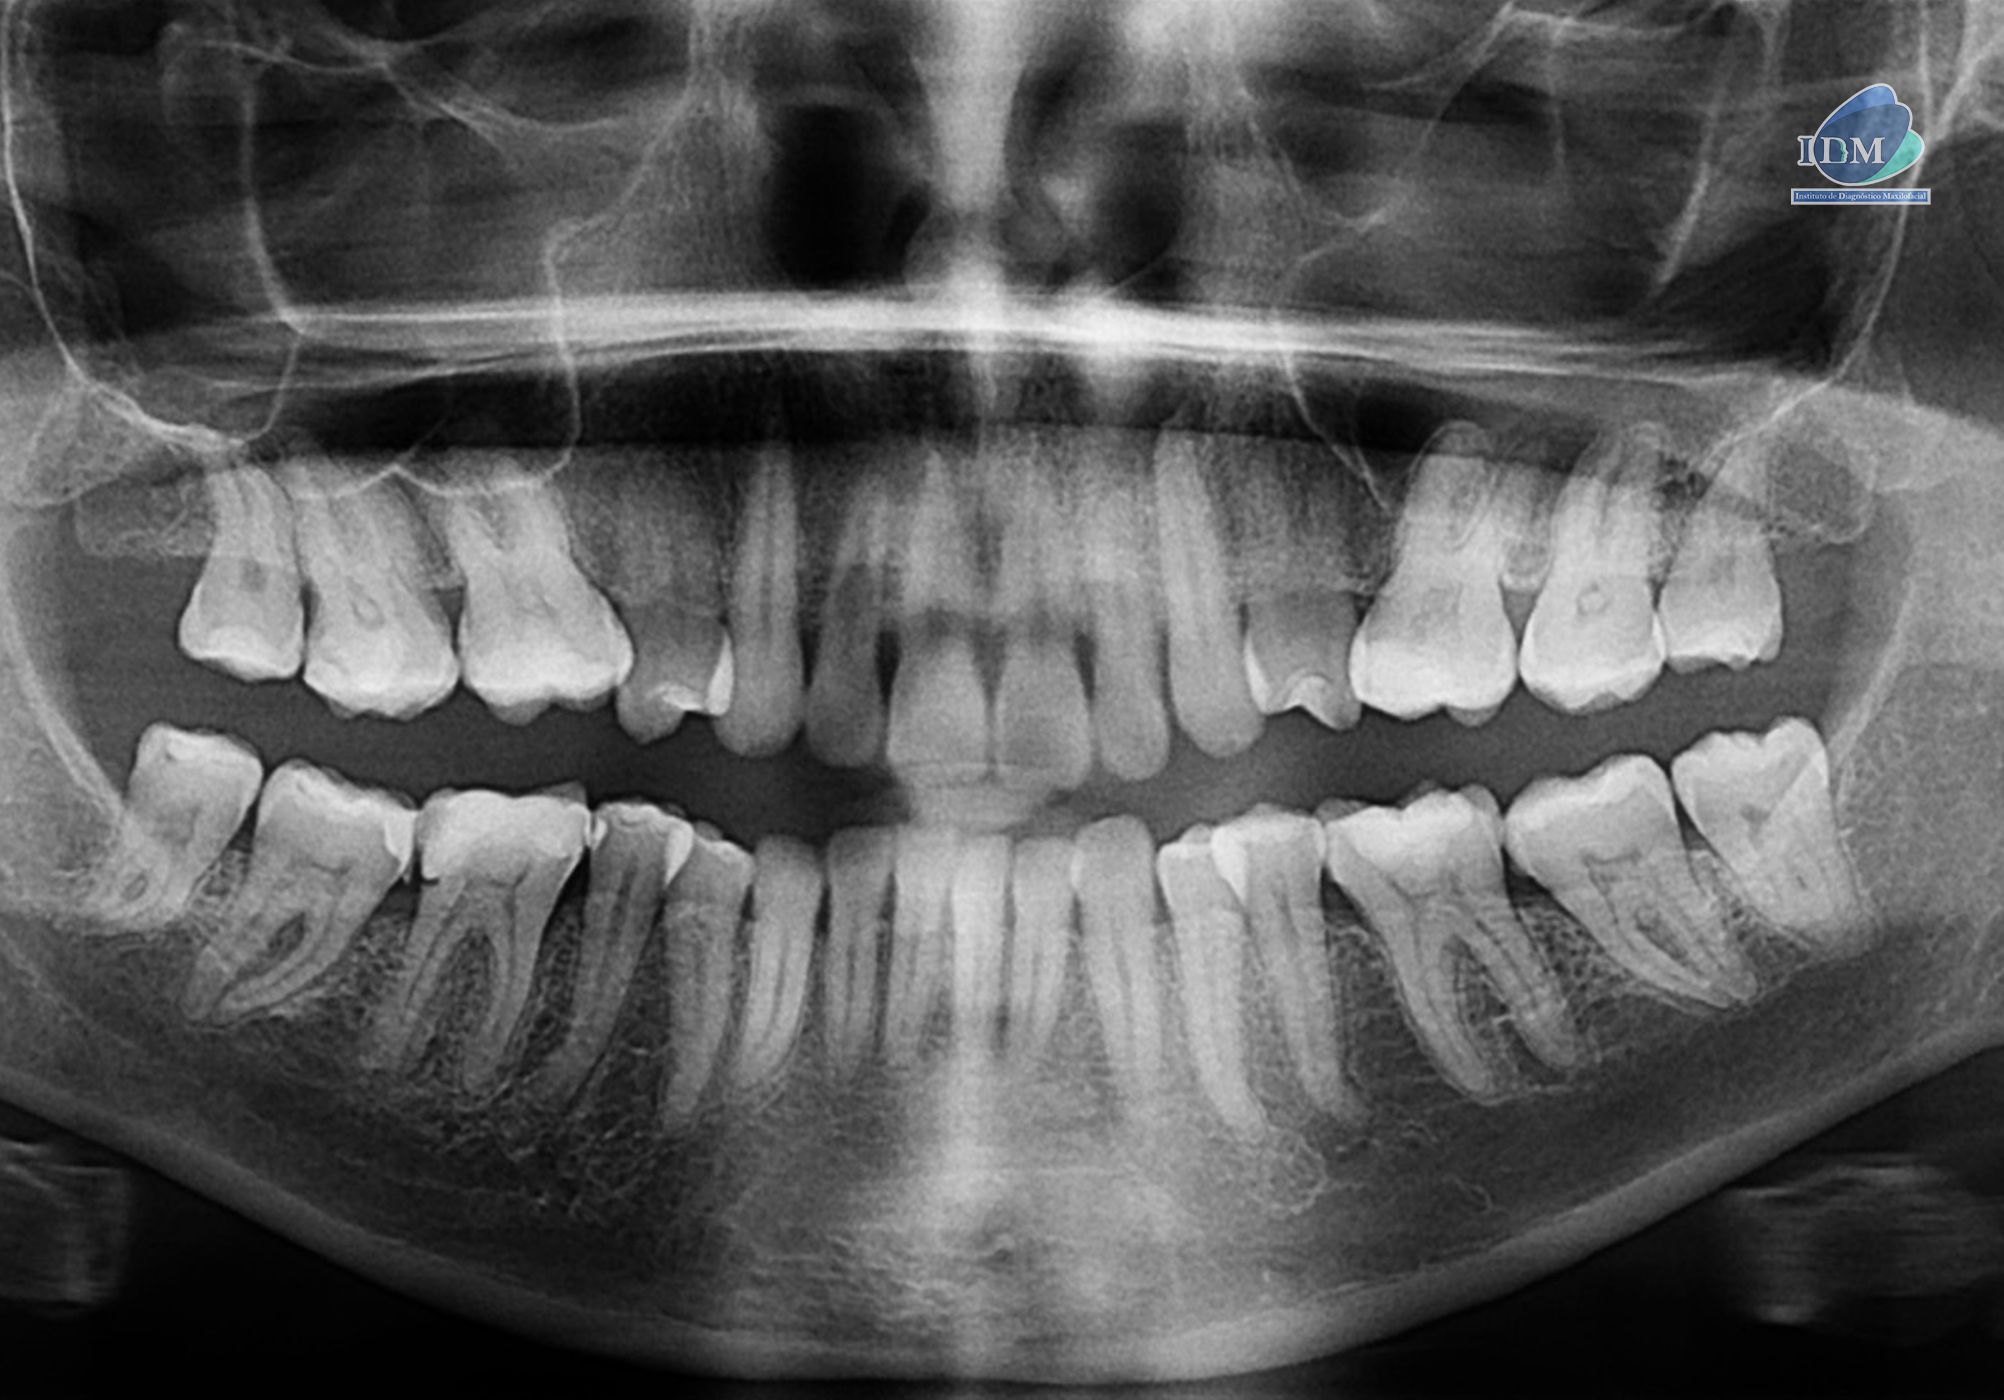

Radiografia Panorámica

En la radiografía panorámica (Figura 1), se aprecia imagen radiolúcida unilocular, proyectada a nivel de tercio apical de pieza 22 y 23, de limites definidos, bordes parcialmente corticalizados.